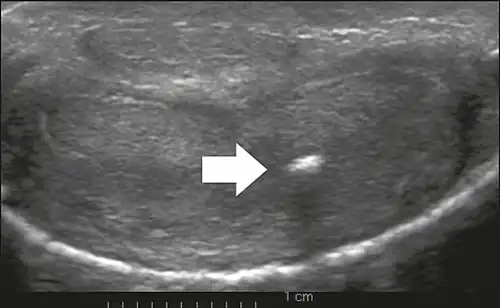

On penile ultrasonography, the typical appearance is hyperechoic focal thickening of the tunica albuginea. Due to associated calcifications, the imaging of patients with Peyronie's disease shows acoustic shadowing, as illustrated in figures below. Less common findings, attributed to earlier stages of the disease (still mild fibrosis), are hypoechoic lesions with focal thickening of the paracavernous tissues, echoic focal thickening of the tunica without posterior acoustic shadowing, retractile isoechoic lesions with posterior attenuation of the beam, and focal loss of the continuity of the tunica albuginea.

In the Doppler study, increased flow around the plaques can suggest inflammatory activity and the absence of flow can suggest disease stability. Ultrasound is useful for the identification of lesions and to determine their relationship with the neurovascular bundle. Individuals with Peyronie's disease can present with erectile dysfunction, often related to venous leakage, due to insufficient drainage at the site of the plaque. Although plaques are more common on the dorsum of the penis, they can also be seen on the ventral face, lateral face, or septum.[14]

Transverse ultrasound of the penis, in a ventral view, in the middle portion of the penis. Note the echoic image with posterior acoustic shadowing, corresponding to calcification (arrow), in the left corpus cavernosum.[14]